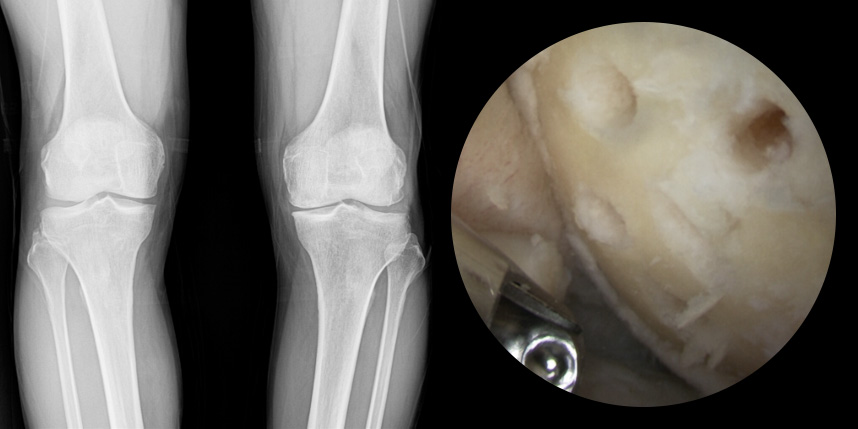

연골손상의 단계를 결정할 때 사용하는 ICRS 단계에서 3단계 미만의 연골손상에 사용하는 방법으로 울퉁불퉁한 표면을 다듬어 주는 정도의 수술법입니다.

4단계 이상일 경우 미세천공술을 기본으로 시행하며, 미세천공술로 나온 본인의 골수줄기세포와 함께

연골 생성을 촉진할 수 있는 “재료”를 같이 주입하는 치료를 시행합니다.

손상된 연골 부위에 작은 구멍을 뚫어 골수에서 나오는 줄기세포를 이용하여 연골 재생을 유도하는 방법으로 근본적으로 섬유연골(정상연골보다는 약한 연골)로 재생된다고 알려져 있습니다.

특수하게 농축하여 제작된 6% 콜라겐(리젠실603) 또는 9% 콜라겐(이엔카티)을 천공술을 시행한 부위에 덮어 주어 미세천공술 단독보다 좋은 치료 결과를 기대할 수 있습니다.

본원에서는 미세천공술, 콜라겐주입술, 카티스템 치료를 주로 하고 있습니다.

연골 손상이 크거나 작고 어느 위치에 있어도 연골재생술이 가능합니다.

전통적으로 증명이 된 미세천공술을 항상 같이 시행

타병원 미세천공술 실패 후 통증으로 내원하신 사례